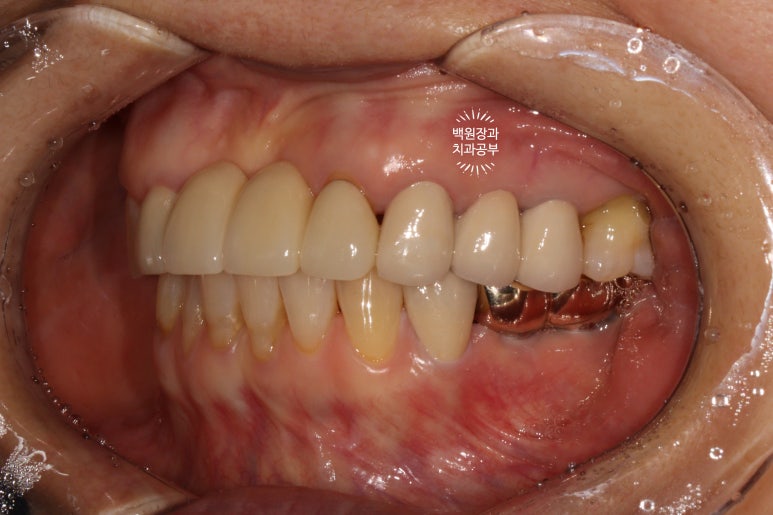

수술 전의 사진과 비교해서 생각보다 임플란트가 원래 자리와 비슷한 레벨에 위치해 있음을 확인할 수 있습니다.

이게 모두 임플란트 제거와 동시에 시행했던 덴티움 뼈이식재를 이용한 치조골 이식술 덕분입니다.

정면에서 보았을 때는 잘 보이시지 않을 수 있으나,

측면에서 보았을 때, 처음에 저희 병원에 내원하셨을 때에 비해 많이 길어지지 않고 비슷한 길이의 크라운으로 제작된 것을 확인하실 수 있을겁니다.

수술 전에 비해 약 1-2mm 정도 임플란트 크라운이 길어진 느낌이네요.

체감이 잘 안되실 수 있으나... 치과의사들이 보면 나름 흥미로움을 느낄 수 있는 결과라고 할 수 있죠!

좌측은 깔끔하게 마무리된 지르코니아 브릿지를 보실 수 있네요 :)